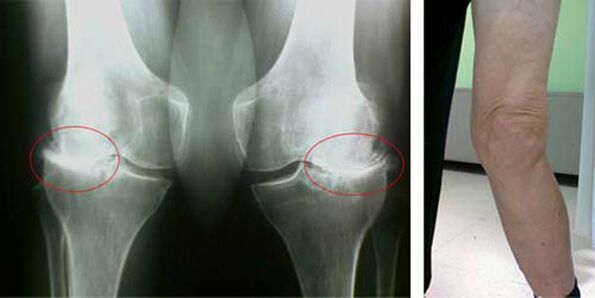

Diz ekleminin artrozu gibi bir patolojinin ortaya çıkmasının ilk aşamaları, kendilerini hiçbir şekilde görsel olarak göstermez. Bununla birlikte, belirli bir süre sonra hasta, diz deformitesi belirtilerinin yanı sıra alt bacağın ekseni boyunca (içe doğru) karakteristik bir eğrilik olduğunu fark eder. Bacağınızı bükmeniz gerektiğinde de bir gevreklik var.

Ağrının varlığı, dizde sınırlı hareket, kişinin bir doktora görünmesini ve muayene olmasını sağlar. Bunu yapmak için testleri geçmesi ve hastalıklı eklemin röntgenini çekmesi gerekiyor. Bu önlemler diz ekleminin artrozunu doğrulamak için yeterli değilse, manyetik rezonans görüntüleme yapılır. Toplanan verilere dayanarak, doktor en iyi tedavi yöntemlerini seçer.